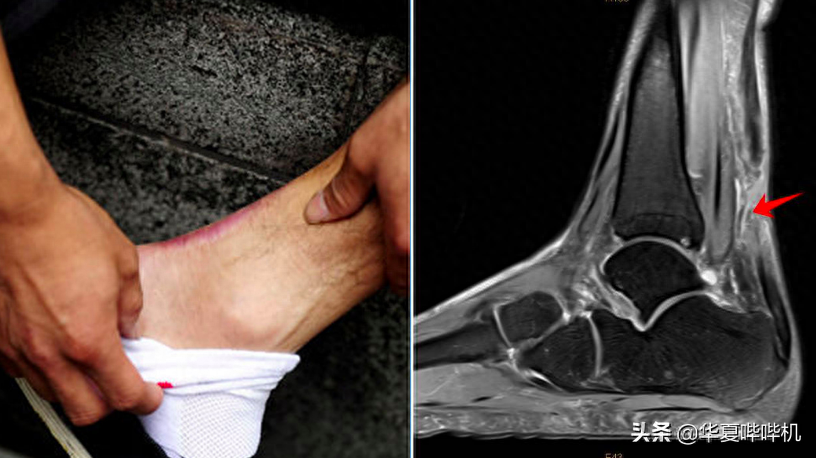

2002年初,正处于春风得意时期的张尚武遇上了刘翔同款伤病——训练中突然左脚跟腱断裂。

突如其来的变故不仅让张尚武被剔除雅典运动会名单,也相当于给他的国家运动员生涯提前吹响了结束的号角,张尚武只能满怀不甘回到了省队,原想着能够卷土重来,再次回到国家队效力,奈何他的跟腱恢复不佳,让张尚武的成绩难回往日高度。